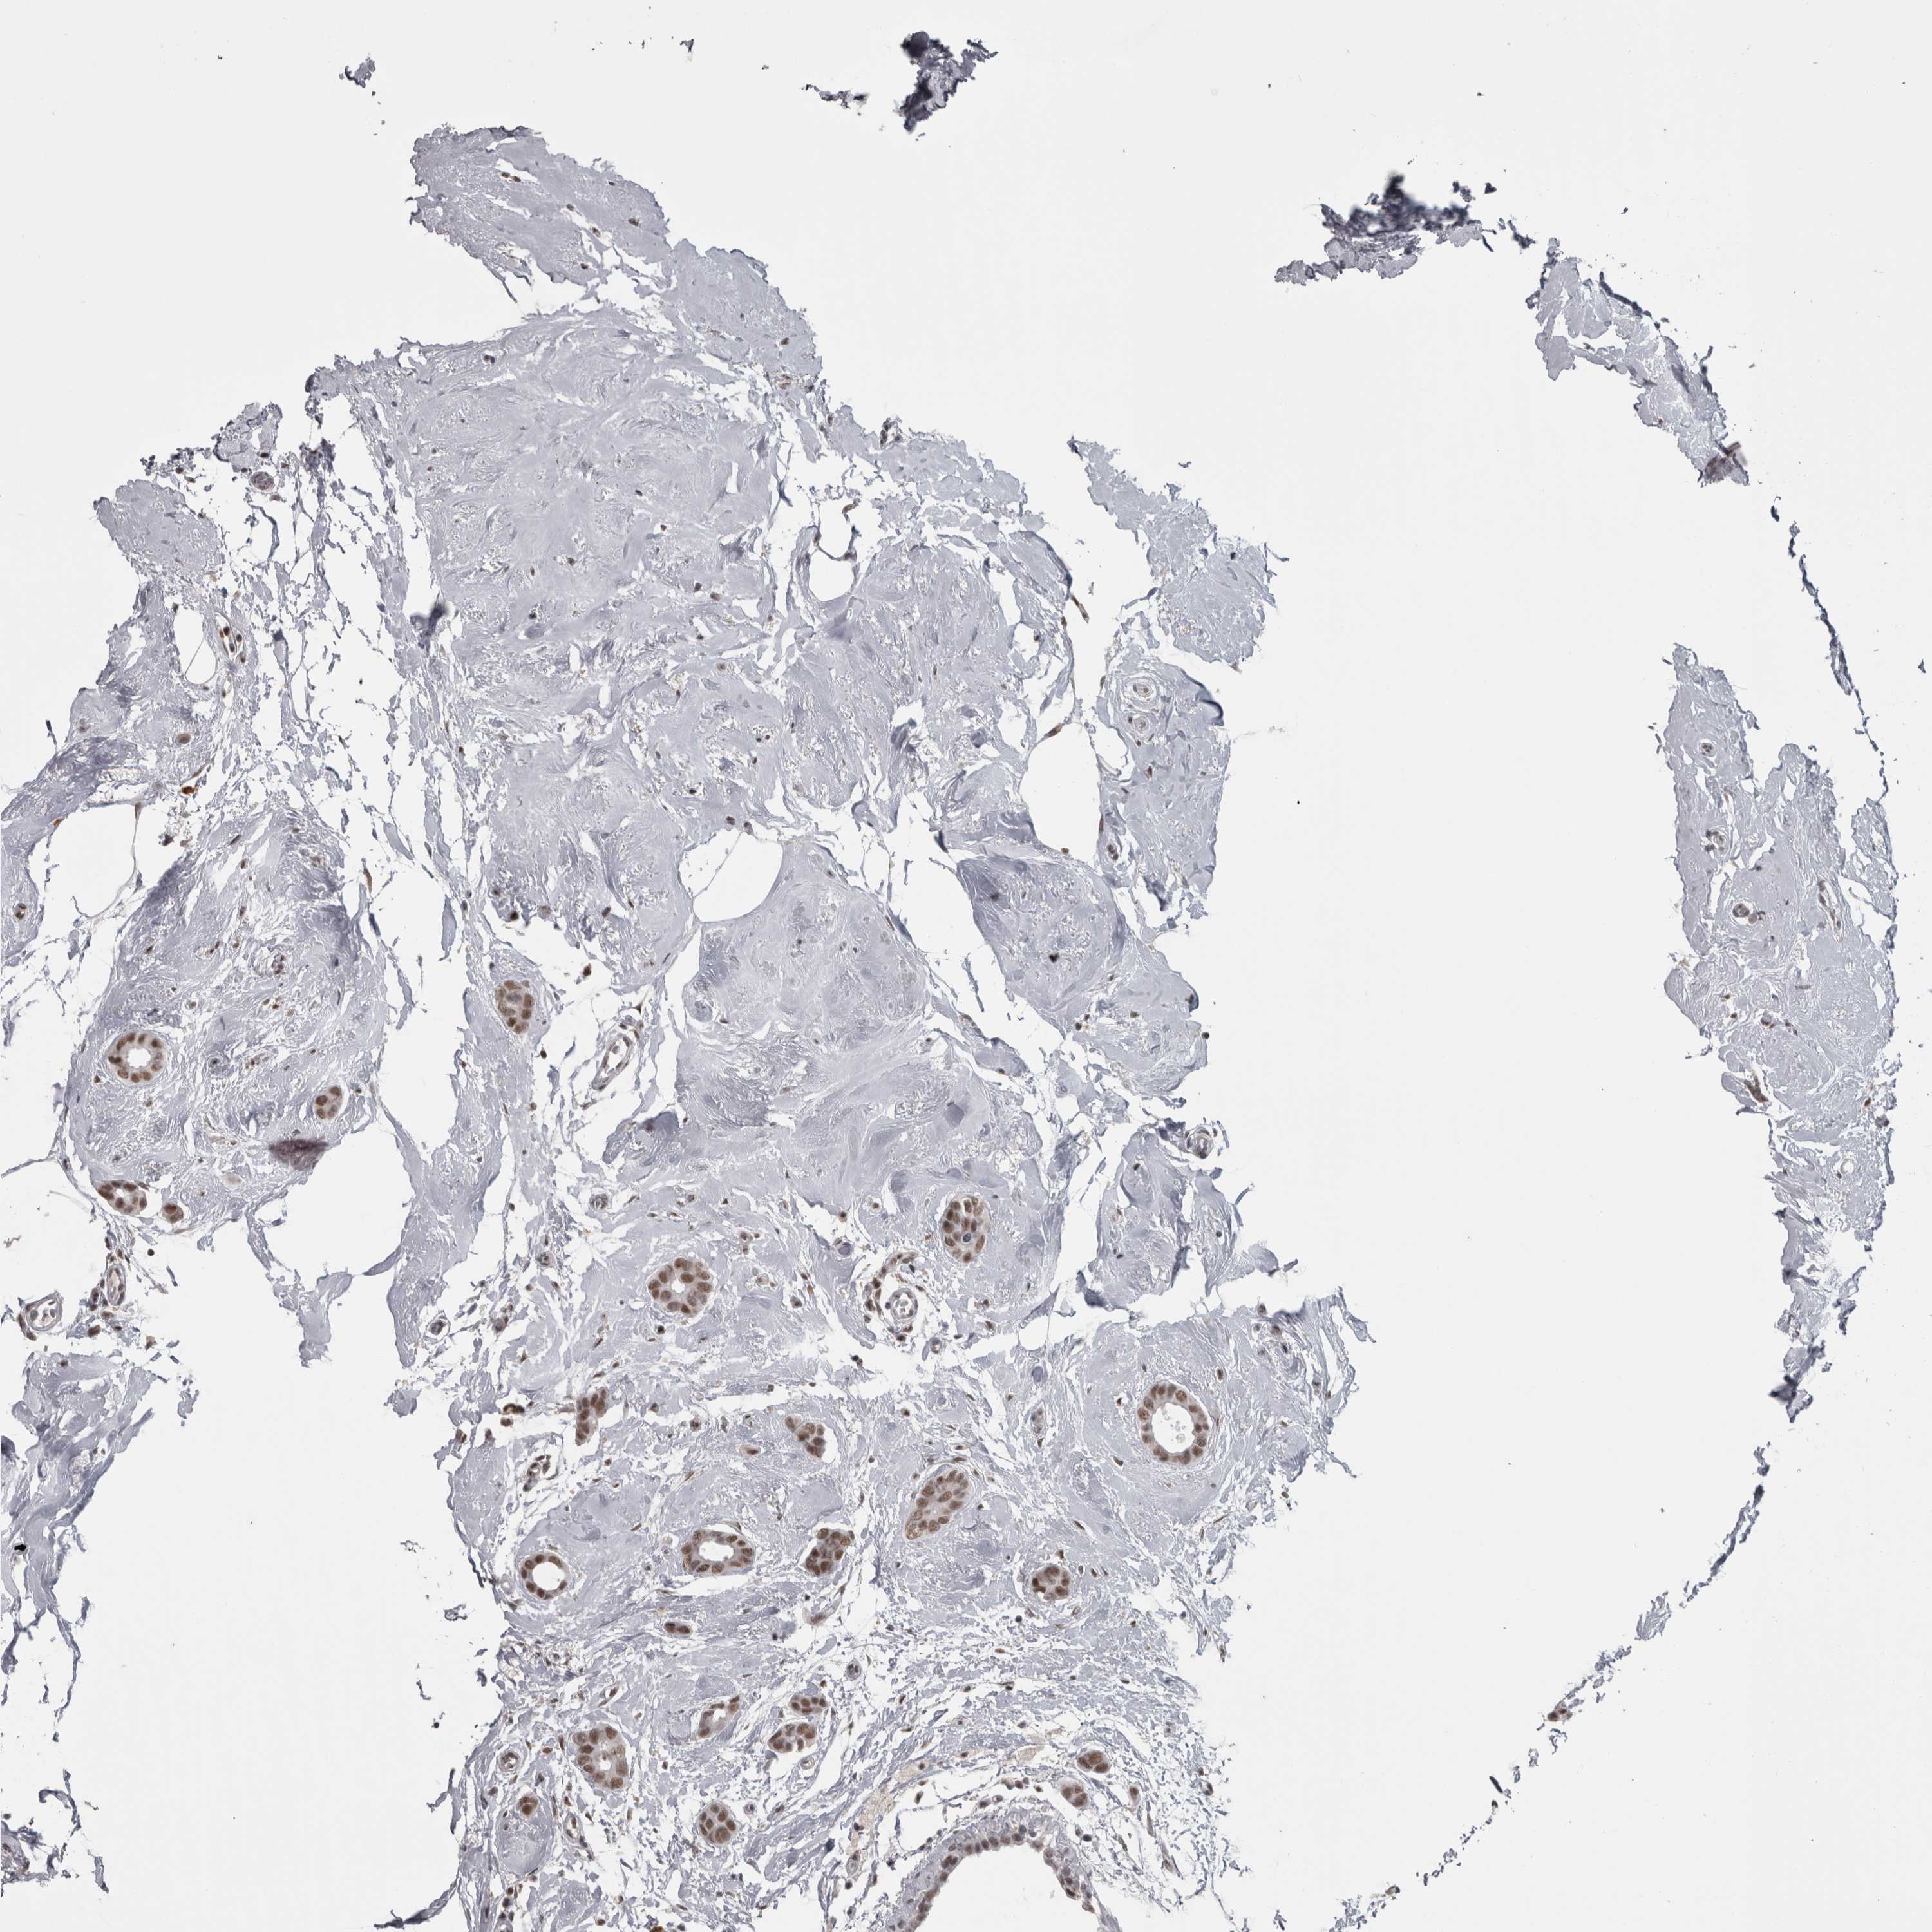

BRCA TCGA BRCA VALIDATION PROTEIN EXPRESSION

ANTIBODIES

AND

VALIDATION